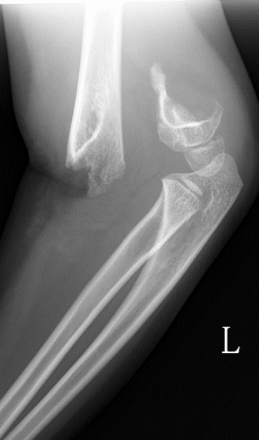

1、小红(化名):女、6岁、吊单杠时不慎摔伤致左肘部肿痛、畸形、活动受限2小时就诊我院。(下图为患儿术前X线片及CT检查)

此种类型的骨折称为肱骨髁上骨折,在完善相关辅助检查后予行麻醉下平乐郭氏手法正骨经皮钢针内固定治疗,术后患儿恢复良好,手术部位只有几个小针眼。(下图为患儿术后X线片)